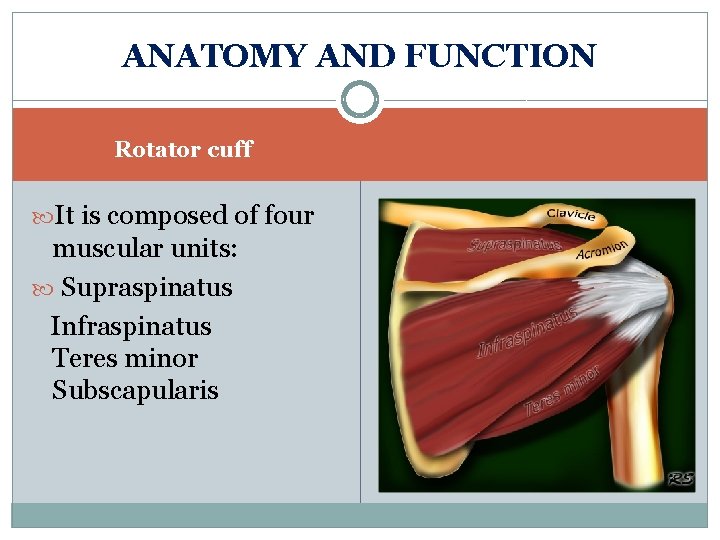

ANATOMY AND FUNCTION Rotator cuff It is composed of four muscular units: Supraspinatus Infraspinatus Teres minor Subscapularis

Biomechanics of the shoulder Movement is created by the 4 RC. Muscles, originate from the scapula & insert at the greater tuberosity Supraspinatus Initiates Abd Infraspinatus Initiates Ex. R Subscapularis Initiates In. R Teres minor Initiates Add ü Movement is facilitated by a subacromial bursa, lies above supraspinatus muscle ü RC. plays a significant role in stabilizing the GH J.